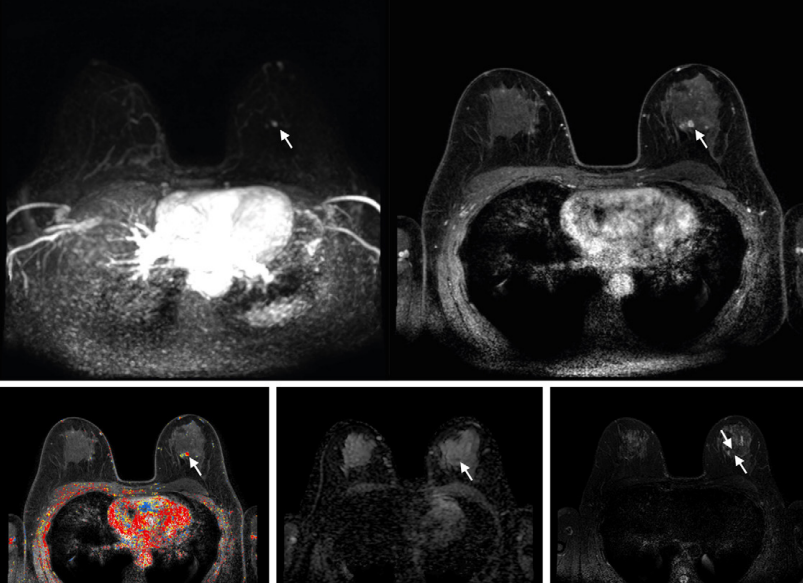

Demonstration of colocalization of pre-existing calcification and incident intraplaque hemorrhage (IPH) in the same plaque. Axial cross sections of the same plaque at the same arterial location on a scan obtained with a T1-weighted gradient-echo noncontrast MRI sequence in a 70-year-old female participant who was free of coronary heart disease and stroke before follow-up MRI. Baseline (left) and follow-up (right) MRI examinations. The blue arrows highlight calcification in a hypointense signal area, while the green arrow indicates IPH as a hyperintense signal. The asterisks mark the lumen of the carotid artery.RSNA